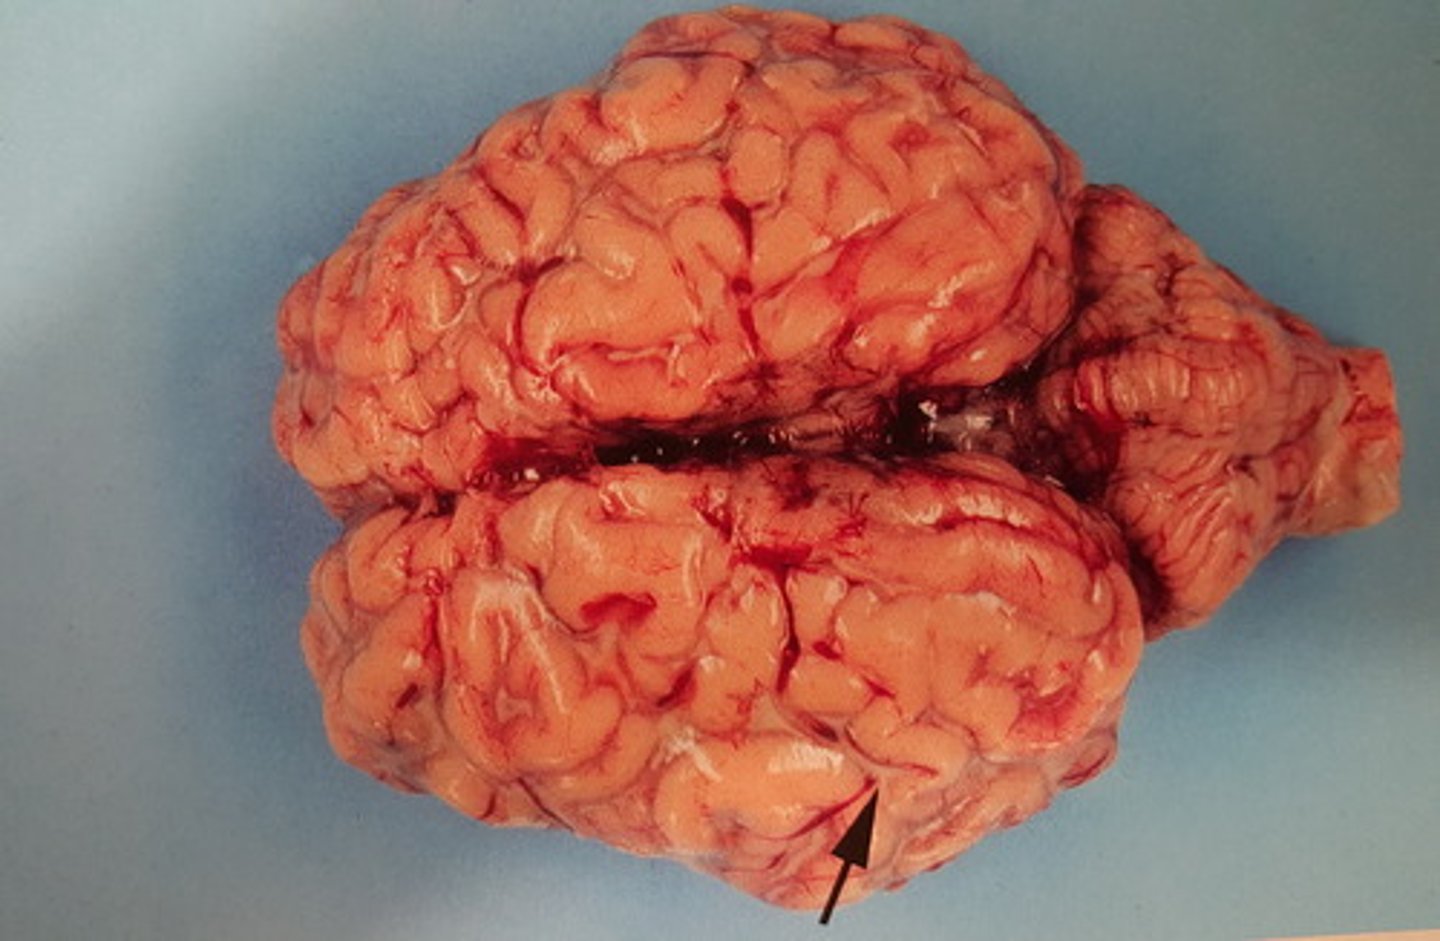

akut, stedvis diffus, fibrinopurulent leptomeningitis

Hjerne fra okse. Patoanatomisk diagnose?

akut diffus purulent leptomeningitis.

Septikæmi med E. coli

Hjerne fra okse. Patoanatomisk diagnose? Ætiologi?

akut, diffus leptomeningitis.

Inflammation karakteriseret med ødem og hyperæmi

Hjerne fra okse. Patoanatomisk diagnose?